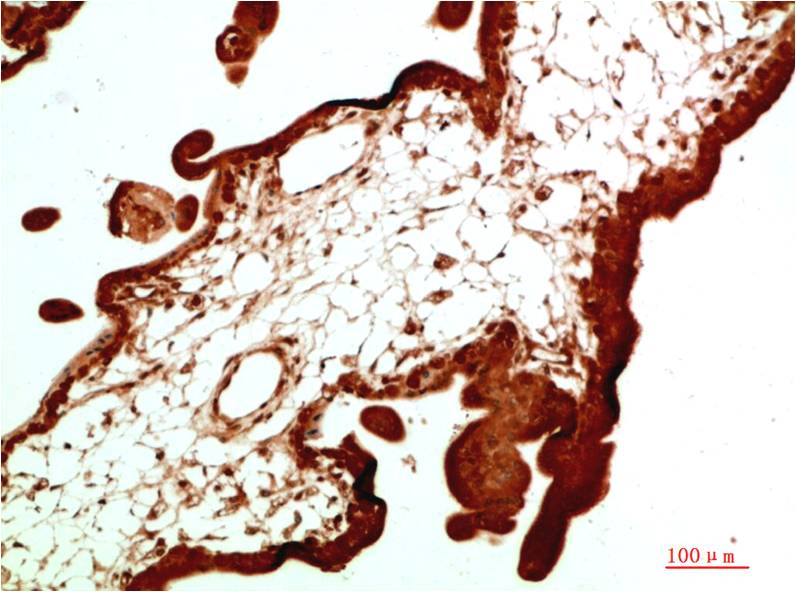

TTR Mouse Monoclonal Antibody(5G9)

Applications :WB, IHC

Prealbumin, also designated transthyretin, is a major thyroid-hormone binding protein involved in transporting thyroxine from the bloodstream to the brain. Prealbumin is located in the cytoplasm and in the vesicles of developing rat brain cells, and is thought to be transported there from the cerebrospinal fluid via endocytosis.

| Recommended dilutions: | WB 1:1,000-2,000 IHC 1:100-200 |

| Specificity: | The TTR Mouse Monoclonal Antibody can detects endogenous TTR proteins. |